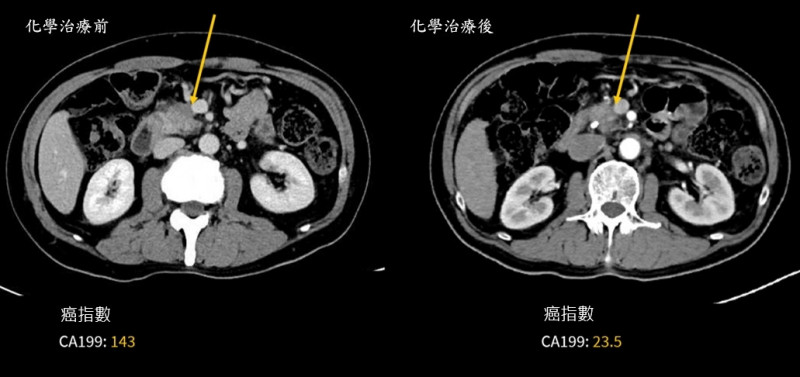

〔記者王俊忠/台南報導〕62歲王先生出現體重減輕與黃疸症狀,經檢查確診為胰臟(俗稱腰尺)癌,影像顯示腫瘤已侵犯肝門靜脈,屬於「邊界可切除」階段。過去這類病人往往難以直接手術、預後也較差。成大醫院外科團隊多專科評估後,王男接受「術前化學治療合併擴大胰臟切除手術」,歷經4個月化療,腫瘤明顯縮小,順利完成合併血管重建的胰十二指腸切除術,術後追蹤2年,患者恢復良好、生活如常。